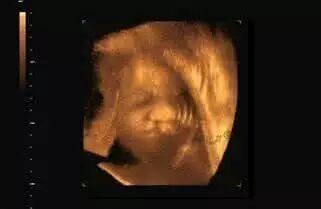

胎儿唇裂

胎儿唇裂就是我们俗称的“兔唇”即唇腭裂,又称缺嘴、豁嘴,是口腔颌面部常见的先天性畸形。有关统计表明,目前我国新生儿兔唇的发病率约为1.82‰,全国现有患者170多万,已经成为先天性畸形中最为常见的病症之一。

唇裂是一种常见的先天性畸形。每出生600~700个新生儿就有一个唇裂患儿,给家庭和社会带来沉重的心理负担和经济负担。发病原因主要是由于胚胎口腔的唇部和腭部的中胚叶组织在早期(妊娠前三个月)发生发育暂停所致。病因主要可以概括分为遗传原因和环境原因两大类。 伴随着生活水平和对美学认知程度的不断提高,且每个家庭只有1-2个孩子,患儿及家长都希望获得满意的治疗,这要求我们提高唇腭裂的治疗水平,传统单一的唇腭裂修复手术已不能达到这一目的。从而形成了恢复正常解剖生理功能的,包括矫形-外科-正畸-语音的立体的治疗模式,即唇腭裂多学科的序列治疗。